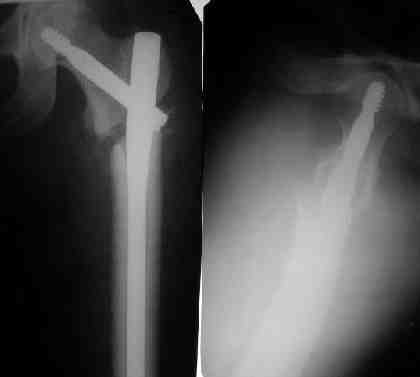

При межвертельных переломах с цефаломедуллярными гвоздями бывает, что проксимальый винт проходит или черед периферический отломок, или прямо над ним. И если остался диастаз, то этот винт при осевой нагрузке не дает сблизиться отломкам. Пример такого остеосинтеза в застарелом случае в приложении.

В качестве предупреждающей меры можно долотом разрушить латеральную стенку дистального отломка под винтом.